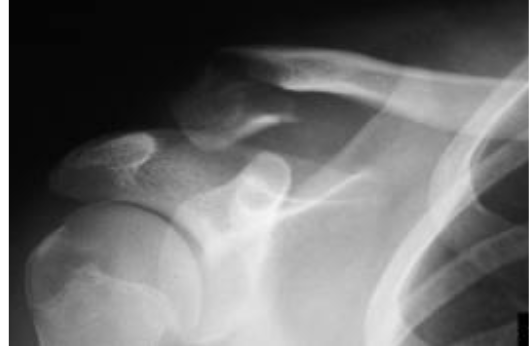

Scapular Fractures

These fractures are normally found after high energy trauma, where 50% scapular fractures are due to motor vehicle accidents.